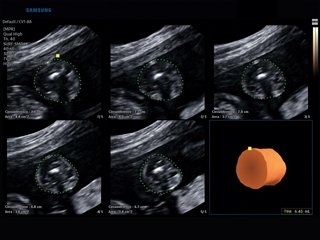

- 5D пакеты (5D Heart, CNS, NT, Follicle, LB, Limb Vol) — точное позиционирование и автоматическая биометрия;

- Пакет опций 5D (5D Heart Color, 5D CNS, 5D NT, 5D LB, 5D Follicle, 5D Limb Vol) — позволяет вывести наиболее значимые проекции структур мозга, сердца плода, а также длинные кости плода при выставлении нескольких маркерных точек и провести в объеме необходимые измерения автоматически;